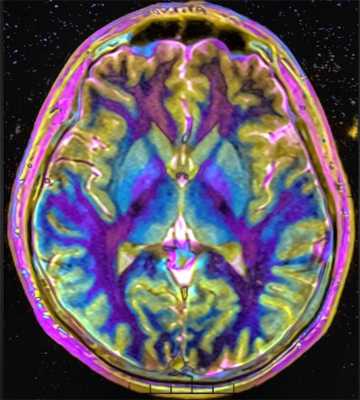

МРТ головного мозга. Т2-взвешенная аксиальная томограмма. Арахноидальная киста. Цветовая обработка изображения.

МРТ головного мозга. Т2-взвешенная аксиальная МРТ. Цветовая обработка изображения.